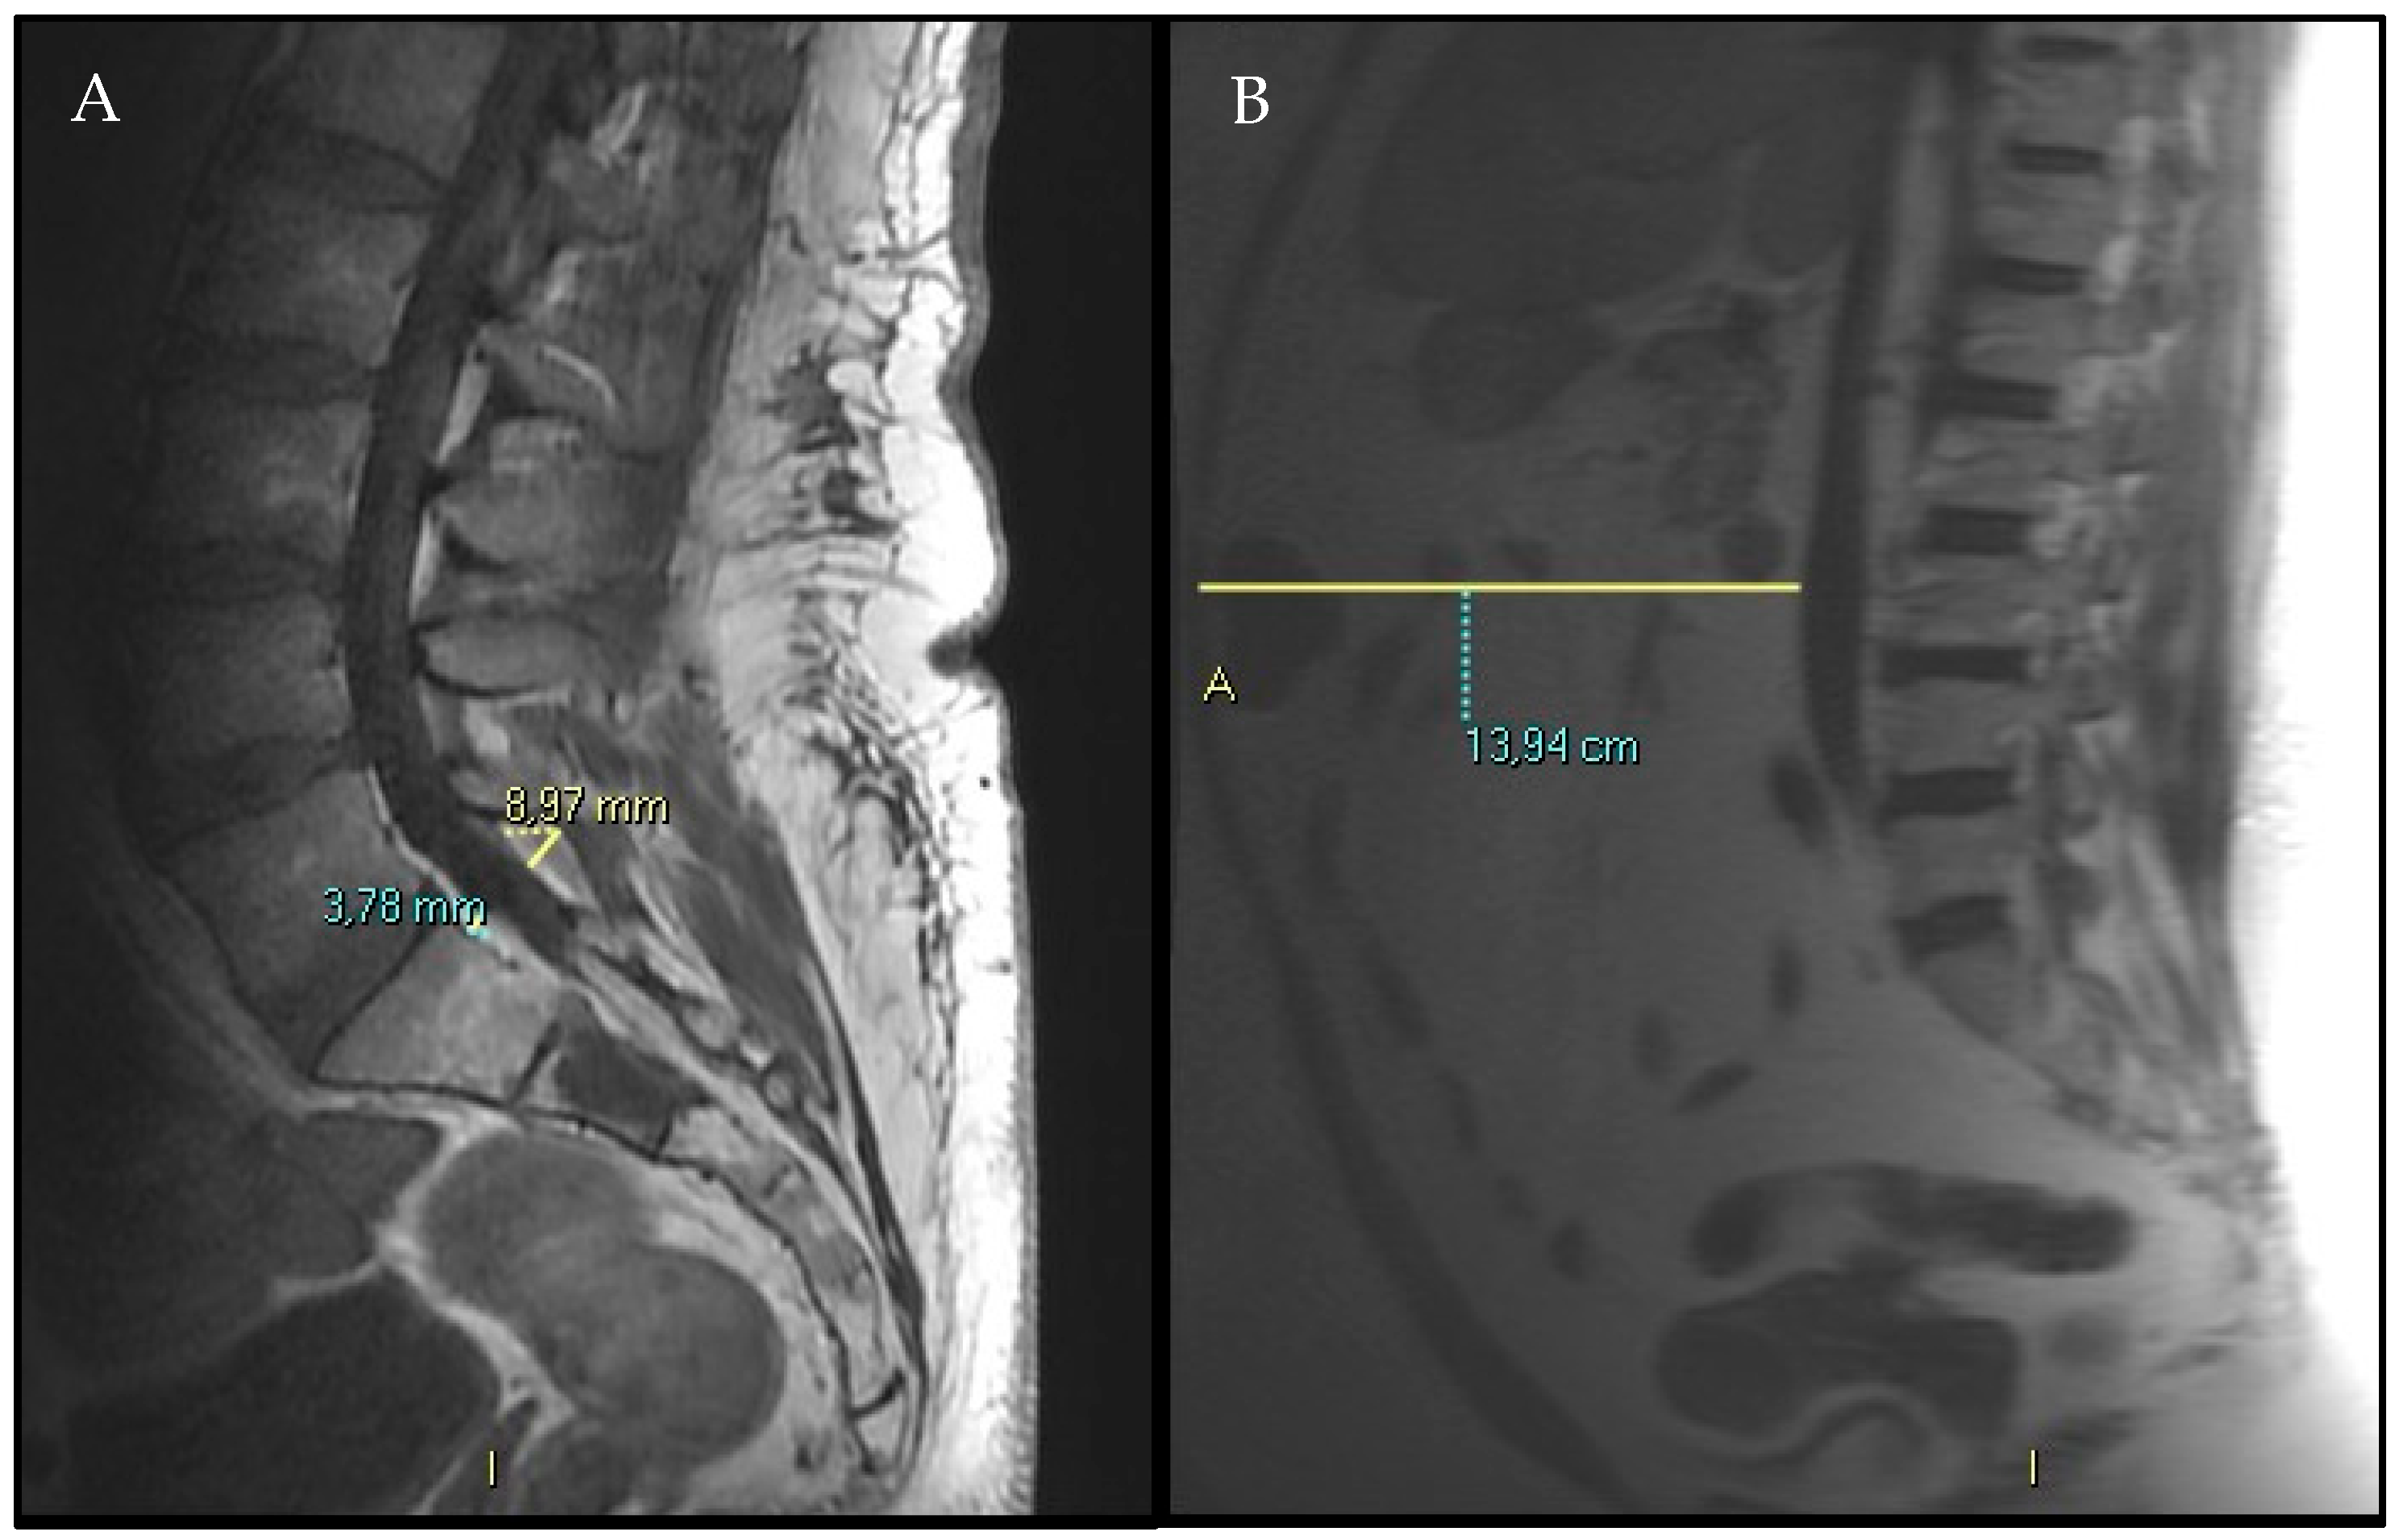

- Spinal canal antero-posterior diameter (SC), at the same level.

- VAT anterior–posterior max diameter at L3 level represented by the distance between the abdominal muscular fascia and the anterior wall of the abdominal aorta at the L3 vertebral level; MR-localizer sequences were used to achieve this aim (Figure 2, panel B).

- SF anterior–posterior diameter has been measured and recorded as well, whether it was comprised in the MR-localizer sequences at the same level (L3), anterior subcutaneous fat pad.